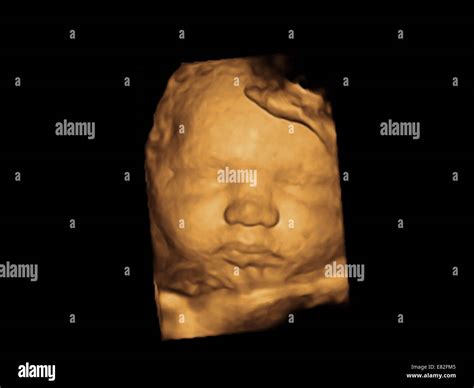

During the 36 Weeks Sonography, several common findings may be observed. Understanding these findings can help expectant parents better comprehend the scan results. Here are some typical observations:

• Organ and System Development: The baby's organs and systems are examined for any abnormalities. At this stage, most organs are fully developed, but any issues can be detected and addressed.

If any abnormalities are detected, the healthcare provider will discuss the findings and recommend appropriate follow-up steps. It's essential to stay calm and ask any questions that may arise during the discussion.